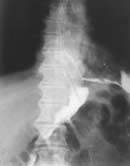

Прямым признаком являлся затек контрастного вещества за пределы исследуемого органа (Рис. 1, 2). Этот симптом на определенных стадиях развития процесса может наблюдаться у всех больных. Выделяют медиастинальный и плевральный затек. Диагностика начальной фазы медиастинального затека сложна. В ряде случаев он выявляется в виде остроконечного выступа в зоне анастомоза. В последующей динамике образуется скопление контрастного вещества в виде бесформенного кармана, ориентированного, как правило, в каудальном направлении. Надо отметить, что диагностика затека, ориентированного перпендикулярно или наклонно к зоне анастомоза, не составляла труда, тогда как выявление распространения контрастного  вещества вдоль стенки желудка или кишки представляло определенные сложности. Таких больных, если позволяла клиническая ситуация, мы осматривали в динамике через несколько часов, когда пищеварительный тракт освобождался от контрастного вещества, а в области затека оно оставалось. При тяжелом состоянии больного и невозможности динамического наблюдения  в экстренном порядке таким больным выполнялась компьютерная томография органов грудной клетки. На компьютерных томограмах  было легче определить, где находится контрастное вещество: вне или внутри пищеварительного канала. Таким образом, удавалось вовремя диагностировать несостоятельность швов анастомоза.

Рис. 1. Медиастинальный затек.